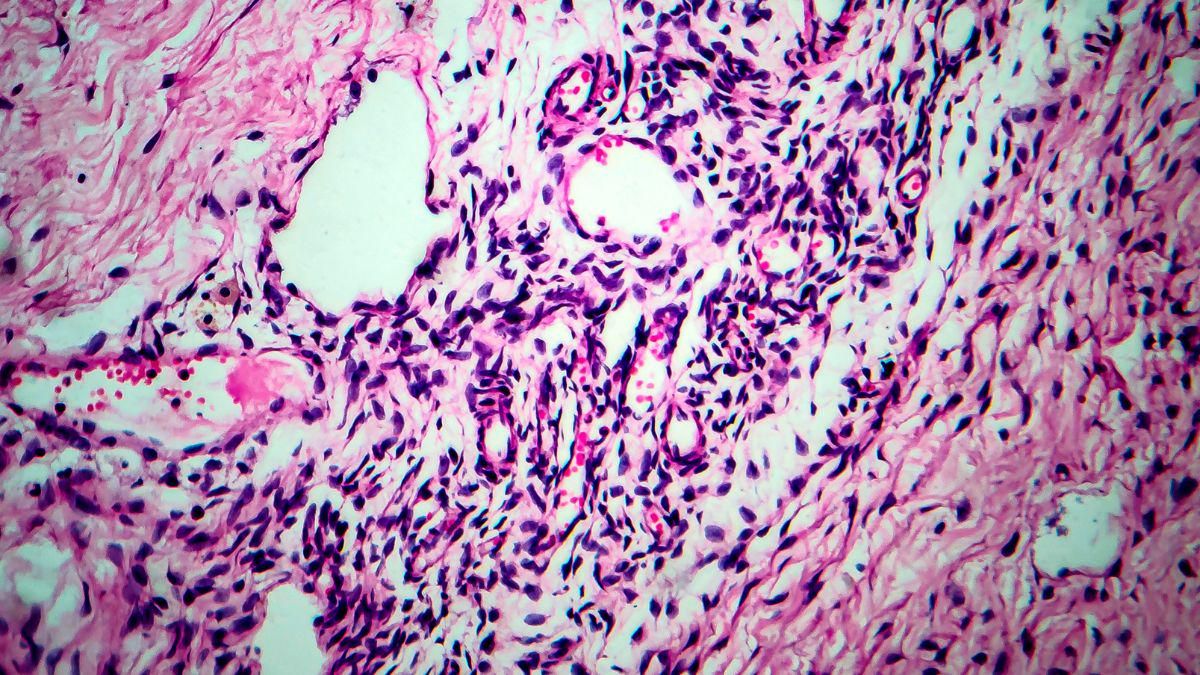

Mengutip Cleveland Clinic, reproduksi sel yang tidak normal dapat menyebabkan munculnya kista seperti dermoid berisi jaringan seperti rambut, kulit, atau gigi. Namun, jenis kista ini tidak ada hubungannya dengan siklus menstruasi.

Reproduksi sel yang tidak normal juga bisa berkembang menjadi kistadenoma. Jenis kista ini kemungkinan terisi oleh bahan berair atau berlendir.

Kista dermoid dan kista denoma bisa berubah menjadi besar dan menggeser ovarium sampai keluar dari posisinya.